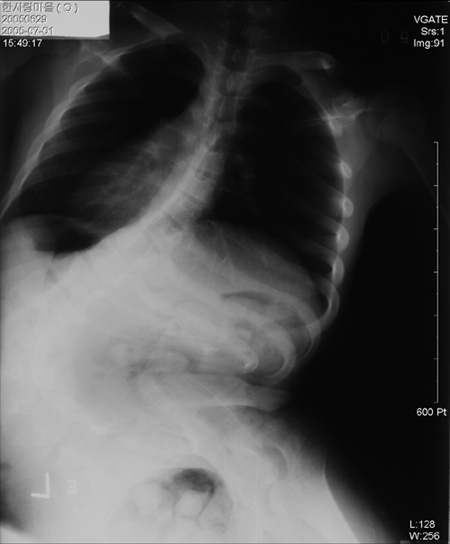

°í·Á´ëÇб³ ±¸·Îº´¿ø ôÃßÃø¸¸Áõ¿¬±¸¼Ò(¼ÒÀå ¼­½Â¿ì Á¤Çü¿Ü°ú ±³¼ö)°¡ 2005³â 6~12¿ù±îÁö 7°³¿ù°£ Àü±¹ 82°³ ±¹°¡µî·Ï Àå¾Ö½Ã¼³ ¾Æµ¿ 1371¸íÀ» ´ë»óÀ¸·Î Á¶»çÇÑ °á°ú, 10¸í Áß 7¸í²ÃÀÎ 988¸í(10µµ ÀÌ»ó)ÀÌ Ã´ÃßÃø¸¸ÁõÀ¸·Î Áø´ÜµÆ´Ù. Ç㸮°¡ 40µµ ÀÌ»ó ÈÖ¾î ½Ã±ÞÈ÷ ¼ö¼úÀ» ¿äÇÏ´Â °æ¿ì°¡ 15%(203¸í), 100µµ ÀÌ»ó ÈÖ¾î ¼ö¼úÁ¶Â÷ ¾î·Á¿î ¾Æµ¿ ¶ÇÇÑ 2%(31¸í)¿¡ ´ÞÇÏ´Â °ÍÀ¸·Î ³ªÅ¸³µ´Ù.

ôÃßÃø¸¸ÁõÀº Ç㸮°¡ CÀÚ ¸ð¾ç ¶Ç´Â SÀÚ ¸ð¾çÀ¸·Î ÈÖ¾îÁö´Â º´À¸·Î ³ú¼º¸¶ºñ ¾î¸°ÀÌÀÇ 90% À̻󿡼­ ¹ß»ýÇÑ´Ù. Ä¡·á Àû±â¸¦ ³õÄ¡°Ô µÇ¸é ±³Á¤Çϱ⵵ Èûµé »Ó ¾Æ´Ï¶ó ¿À·¡ ¹æÄ¡ÇÒ °æ¿ì ½ÉÀå°ú ÆóÀÇ ±â´É ÀúÇϸ¦ ÀÏÀ¸Å³ ¿ì·Á°¡ ÀÖ¾î Á¶±â ¹ß°ßÀÌ ÇʼöÀûÀÎ Áúº´ÀÌ´Ù.

ÀϹÝÀûÀ¸·Î ôÃß°¡ 10µµ ÀÌ»ó ÈÖ°Ô µÇ¸é ôÃßÃø¸¸ÁõÀ¸·Î Áø´Ü¹Þ¾Æ ÀÚ¼¼±³Á¤ Ä¡·á¸¦ ¹Þ¾Æ¾ß Çϰí, 20µµ ÀÌ»ó ÈÖ¸é º¸Á¶±â¸¦ Âø¿ëÇØ »ýÈ°ÇØ¾ß ÇÑ´Ù. 40µµ ÀÌ»óÀ¸·Î Ç㸮°¡ ½ÉÇÏ°Ô ÈÙ °æ¿ì ¼ö¼ú¹Þ¾Æ¾ß ÇÑ´Ù. ôÃß°¡ 40µµ ÀÌ»ó ÈÖ¾îÁø »óÅ¿¡¼­ ¹æÄ¡µÇ¸é 1~2³â »çÀÌ¿¡ 100µµ ÀÌ»ó±îÁö µîÀÌ ±ÁÀ» ¼öµµ ÀÖ¾î °¢º°ÇÑ ÁÖÀǰ¡ ¿ä±¸µÈ´Ù.

Àå¾Ö½Ã¼³ÀÇ ³ú¼º¸¶ºñ ¾Æµ¿µé°°ÀÌ Á¶±âÁø·á°¡ ÀÌ·ïÁöÁö ¾Ê¾Æ Ç㸮 ¸ð½ÀÀÌ CÀÚ ¸ð¾çÀ¸·Î 100µµ ÀÌ»ó ÈÖ°Ô µÇ¸é Àå±â°¡ ¾Ð¹ÚµÊÀº ¹°·Ð ½ÉÀå°ú ÆóÀÇ ±â´ÉÀÌ ÀúÇϵǾî Á¶±â »ç¸ÁÀÇ ¿øÀÎÀÌ µÉ ¼ö ÀÖ´Ù. »Ó¸¸ ¾Æ´Ï¶ó ÈÙü¾î ½Å¼¼Á¶Â÷ Áú ¼ö ¾ø¾î ¹æ¿¡¸¸ ´©¿öÀÖ°Ô µÇ¸ç ÅëÁõ ¶ÇÇÑ ¸»·Î Ç¥ÇöÇÒ ¼ö ¾øÀ» Á¤µµ·Î ½ÉÇÏ´Ù.